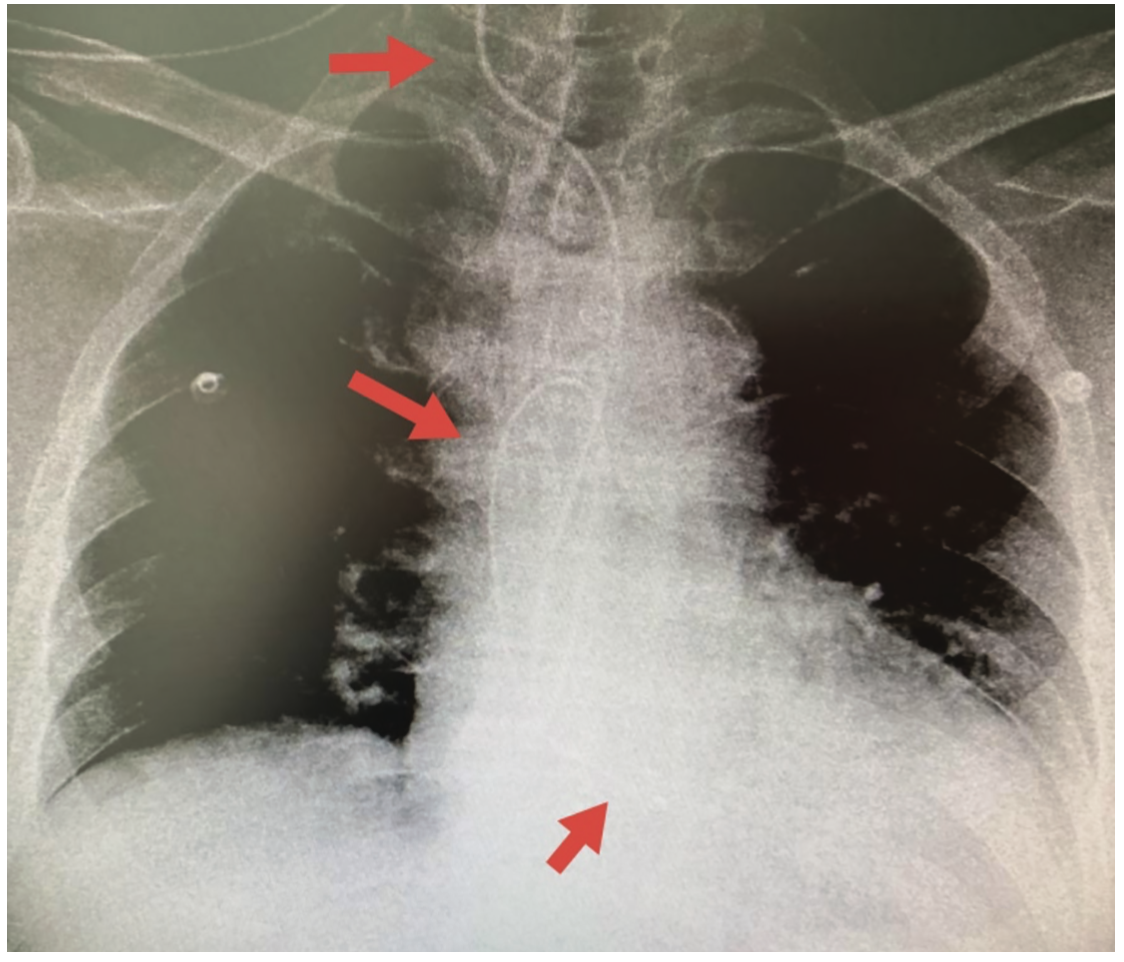

Temporary Pacemaker Chest X Ray . Cardiac pacemakers may be temporary or permanent, with the latter commonly. In 2009, more than 300,000 adults and children in the united states underwent placement of a new pacemaker or icd, and over 150,000 patients underwent revision [1]. transvenous pacing is the preferable method for temporary pacing in the icu, usually placed via internal jugular or subclavian veins. normal and abnormal radiographic appearances of cardiac conduction devices are presented, with. cardiac pacemaker and implantable cardioverter defibrillator (icd) systems are commonly seen on chest radiographs. temporary cardiac pacemaker wire, inserted via a femoral venous route, noted projected over the apex of the right ventricle. These pacemakers are meant for short. 11 chest x ray shows a transvenous pacing electrode into the right ventricle (black arrows).

transvenous pacing is the preferable method for temporary pacing in the icu, usually placed via internal jugular or subclavian veins. normal and abnormal radiographic appearances of cardiac conduction devices are presented, with. Cardiac pacemakers may be temporary or permanent, with the latter commonly. cardiac pacemaker and implantable cardioverter defibrillator (icd) systems are commonly seen on chest radiographs. 11 chest x ray shows a transvenous pacing electrode into the right ventricle (black arrows). In 2009, more than 300,000 adults and children in the united states underwent placement of a new pacemaker or icd, and over 150,000 patients underwent revision [1]. temporary cardiac pacemaker wire, inserted via a femoral venous route, noted projected over the apex of the right ventricle. These pacemakers are meant for short.